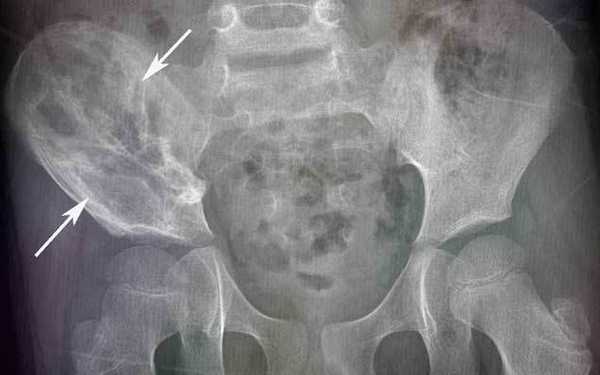

— Рентгенологическое исследование. Позволяет визуализировать тень опухоли, деформацию прилежащих к опухоли фасциальных перемычек, выявить изменения в костях;

Рентгенологические признаки саркомы Юинга:

- поражение кости без четких границ, так называемый симптом «изъеденная молью», чаще распространяется по костномозговому каналу;

- «луковичный периостит» - многослойный периостит, сочетающийся с игольчатым;

- наличие мягкотканного компонента однородной структуры;

- в 5% случаев встречается патологический перелом.